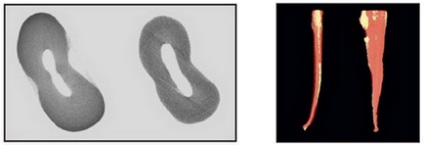

Ábra. 12. A keresztmetszet a gyökér felső kisőrlő ovális gyökérkezelés anatómia (balra) és után (jobbra) szerszám. Mikrokompyuternaya tomográfia.

Ábra. 13. Háromdimenziós rekonstrukció alapján mikroszámítógép tomográfia állkapcsi második premolárisoknál és ovális ívelt gyökérkezelés anatómia. Double Exposure állapot gyökérkezelés a (sárga) és után (piros) szerszám. Ahogy a középső disztális és Bucco nyelvű vetítés mutatja, hogy a anatómiája a gyökércsatorna tartósítva (együtt R. Bedininek és R. Pecci olasz National Institute of Health, Department of Technology és Egészség, Róma, Olaszország).